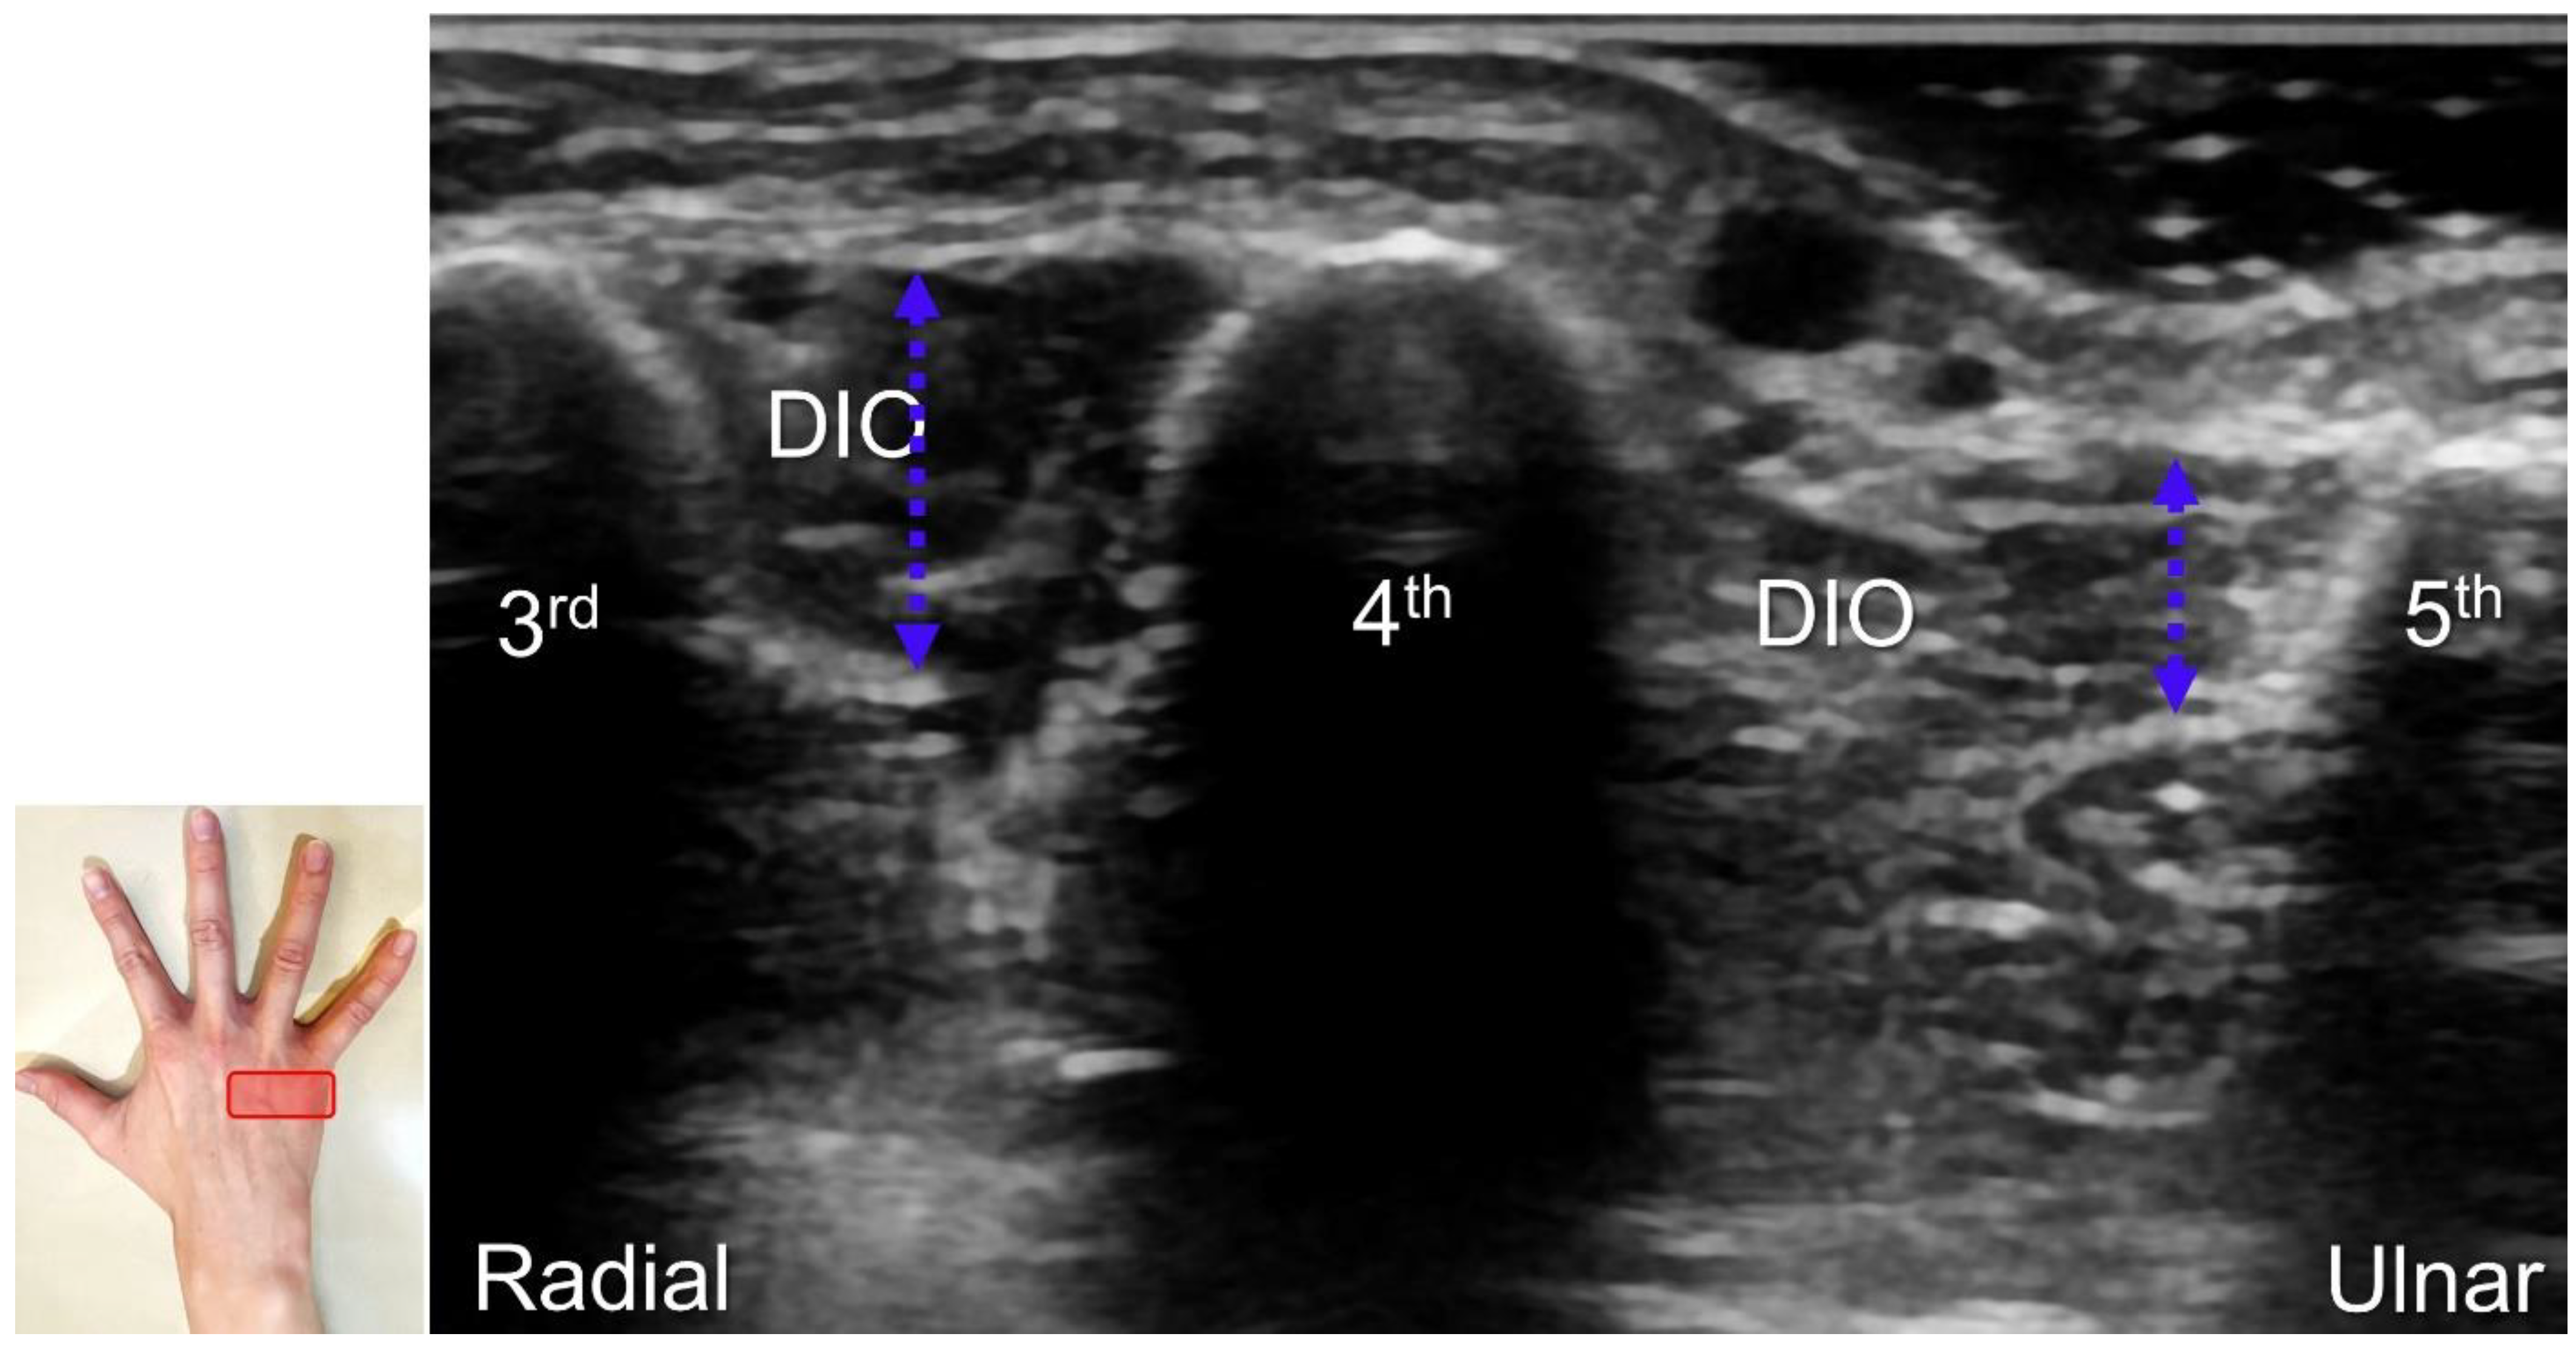

Handlebar neuropathy is a similar scenario that occurs due to continuous compression of the ulnar nerve at the ulnar wrist in cyclists. Focal swelling of the deep branch can be seen at the hamate level. An associated finding would be atrophy/weakness of the dorsal interossei muscles (Figure 16). For treatment, injection over the short axis of the ulnar nerve can be performed using the in-plane approach from the radial aspect in the Guyon’s canal (Figure 17). For certainty, identifying the ulnar artery is essential to prevent iatrogenic injury.

Figure 16. As opposed to the normal third dorsal interossei (DIO) muscle, atrophy in the fourth DIO muscle indicates injury to the terminal branch of the deep branch of the ulnar nerve. Blue double dashed arrows: muscle thickness.